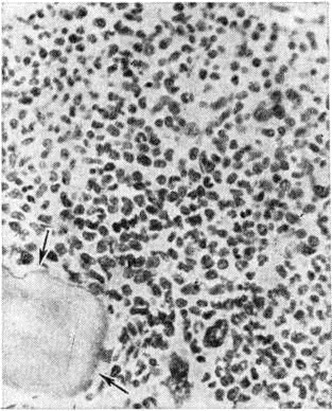

В костном мозге, по данным трепанобиопсии, на первых стадиях заболевания скопления бластных клеток являются очаговыми, в достаточном количестве обнаруживаются элементы деятельного костного мозга. Нередко наблюдаются острые расстройства кровообращения, участки гипоплазии, могут обнаруживаться некрозы. Прогрессирование заболевания характеризуется увеличением числа и размеров лейкозных разрастаний, их слиянием, а затем диффузной инфильтрацией ткани костного мозга. Количество нормальных кроветворных клеток заметно уменьшается. Часто имеется инфильтрация надкостницы, возможно распространение процесса в окружающие мягкие ткани. Развитие лейкозных разрастаний сопровождается выраженным рассасыванием костной ткани, преимущественно по типу гладкой резорбции. Очень редко в этом процессе принимают участие остеокласты. Вследствие частичного, а местами и полного рассасывания костных балок происходит значительное расширение костномозговых полостей, истончение, а в некоторых участках разрушение кортикального слоя. В раннем детском возрасте резкие изменения наблюдаются в зоне энхондрального окостенения. При острых Лейкозы редко отмечается очаговое новообразование атипичной костной ткани, богатой остеоидом, разрастание фиброзной ткани. Наряду с мелкими фокусами некроза иногда возникают обширные инфарктообразные коагуляционные некрозы, определяемые макроскопически в виде жёлто-белых сухих участков; в окружности наблюдаются кровоизлияния, возможно скопление макрофагов (рисунок 1). В области лейкозных разрастаний нередко обнаруживается истончение и частичный распад ретикулярных волокон. Описаны наблюдения с очаговым или диффузным миелофиброзом, который чаще выявляется при миелобластном Лейкозы. В таких случаях при пункции обычно не удаётся получить костный мозг и для установления диагноза необходимо исследование материала трепанобиопсии.